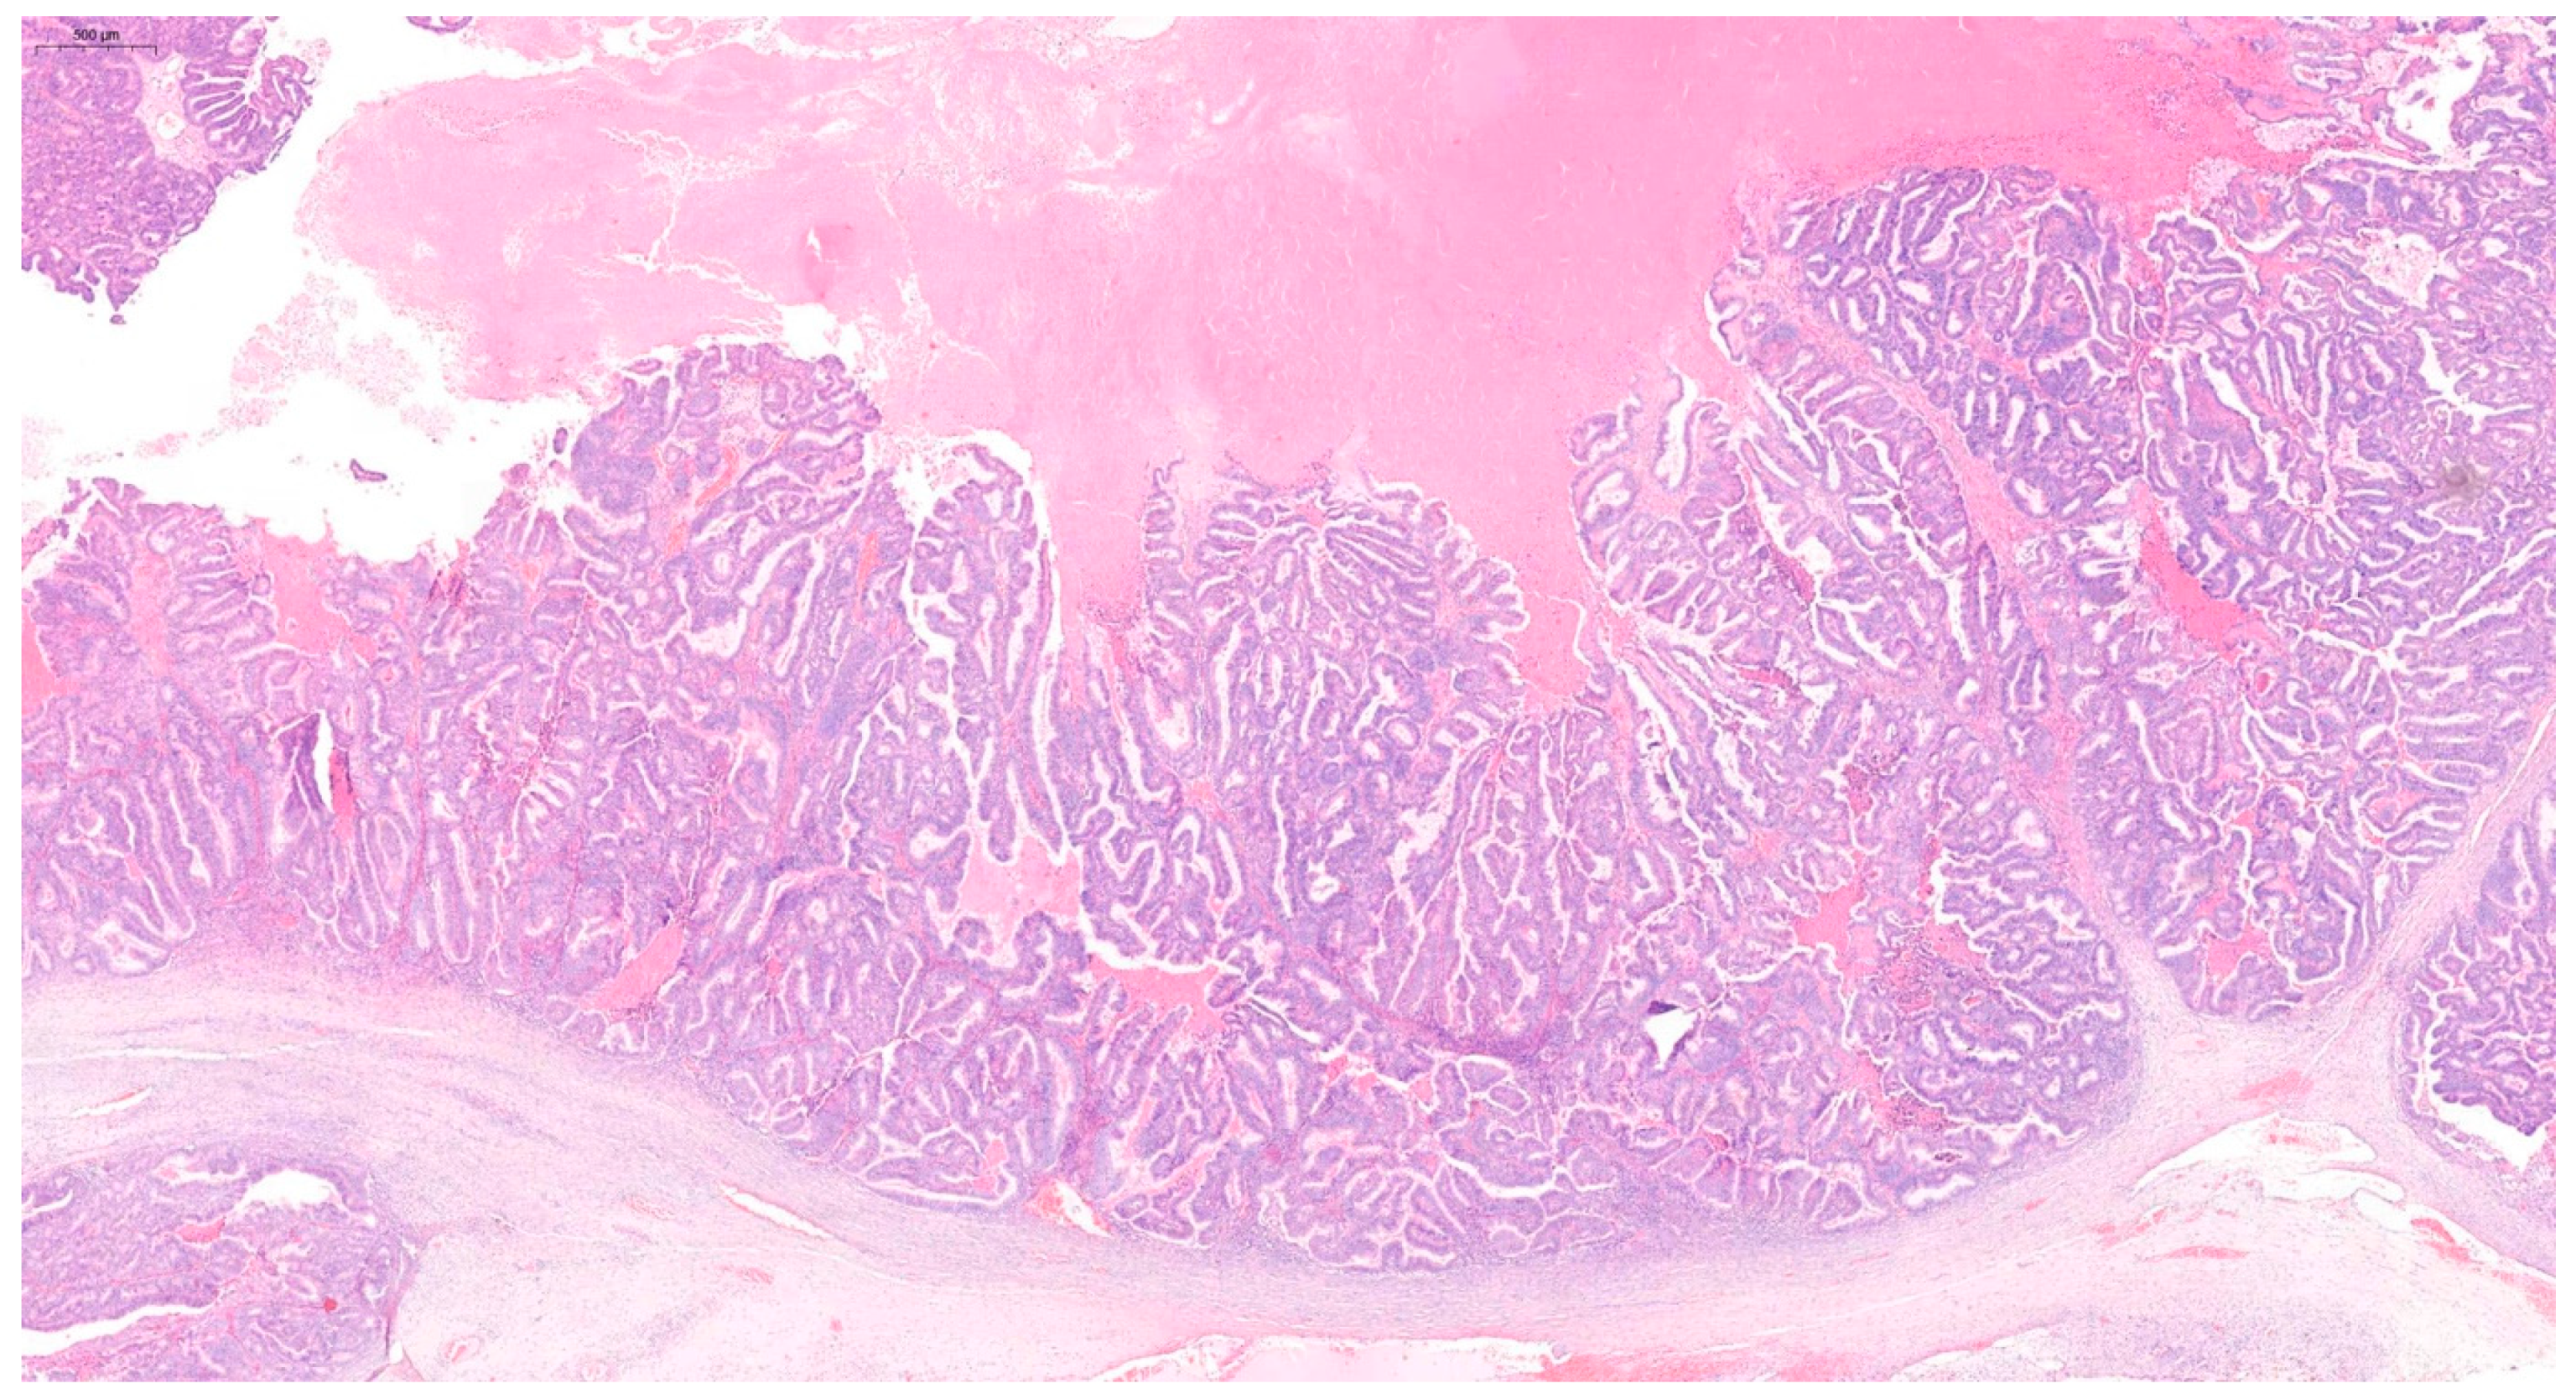

2. Case Report